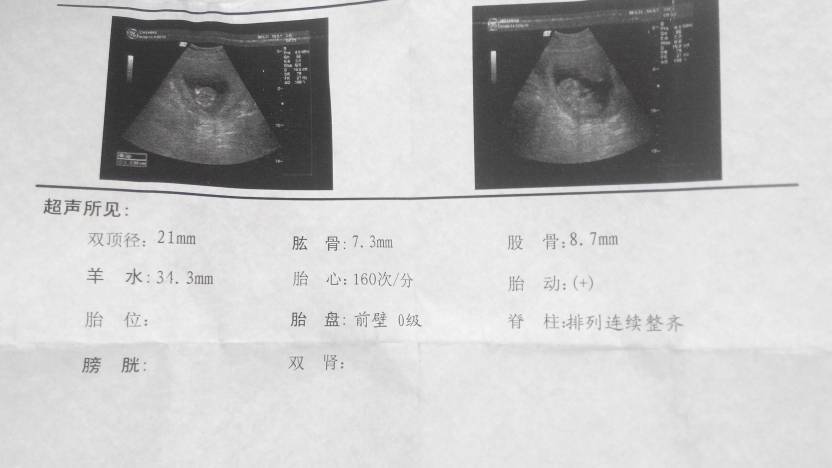

这是胎儿的发育状况数据图

这些都是胎儿的数据。

你好,这是怀孕三个月或快三个月时正常超声报告,双顶径是宝宝的头的直径,肱骨是上臂里最长的骨头,股骨是大腿里最长的骨头。所有数据都是正常范围。这个时间宝宝刚刚成形,胎位是不固定的,膀胱和肾也还不能显示,所以没有报。 现在只要没有什么异常症状, 就好好保养,按时产检就可以了。

从这些数据看,发育很好,不过细节问题这样检查是看不出来的。三个月后做唐低筛查排查智力方面问题,五个月左右做三维或四维彩超,是目前最精确排查发育方面的细节问题。